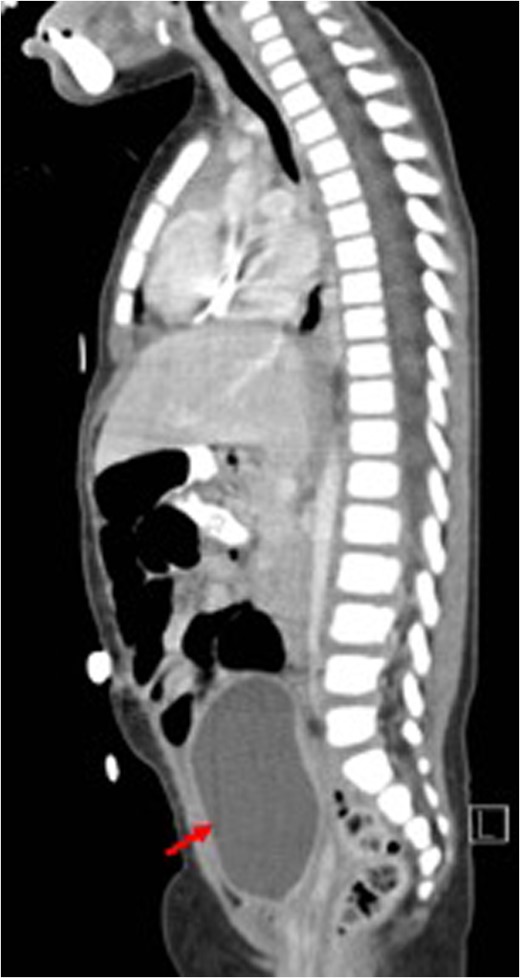

Sagittal view (CT) for the mass (white arrow) post-chemotherapy showing reduction in size (red arrow) bladder.